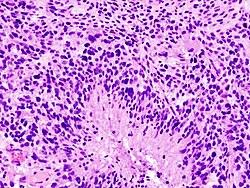

Images

Glioblastoma:

Anaplastic astrocytoma: